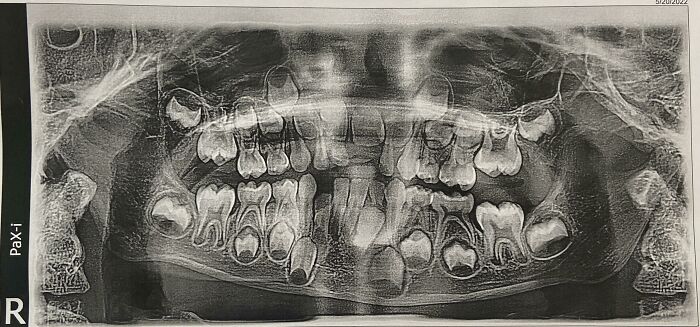

#16 My 6-Years-Old's Dental X-Ray